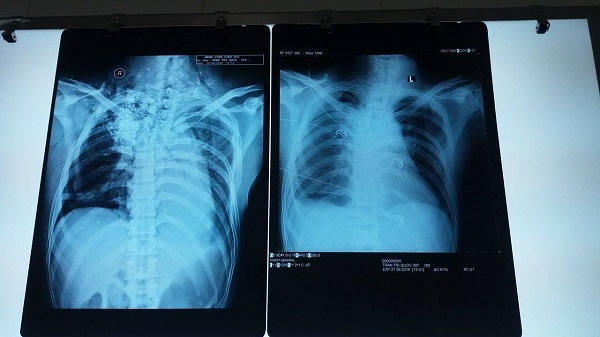

Trao đổi với PV, TS. Bác sĩ Lưu Quang Thùy (phòng Hồi sức tích cực) người trực tiếp điều trị cho anh Quốc cho biết: "Bệnh nhân nhập viện trong tình trạng lơ mơ, bóp bóng qua nội khí quản, liệt hoàn toàn hai chi dưới, mất cảm giác ngang vú, vết thương cổ lưng dài 10 x 40 cm, có nhiều bùn đất ở trong vết thương. Kết quả chụp CT scan và X quang sột sống thắt lưng cho thấy, bệnh nhân bị gẫy cột sống D5-D6 và trượt sang trái, vùng đỉnh phổi và vùng cổ phải có nhiều dị vật là đất cát, tràn máu tràn khí màng phổi trái".